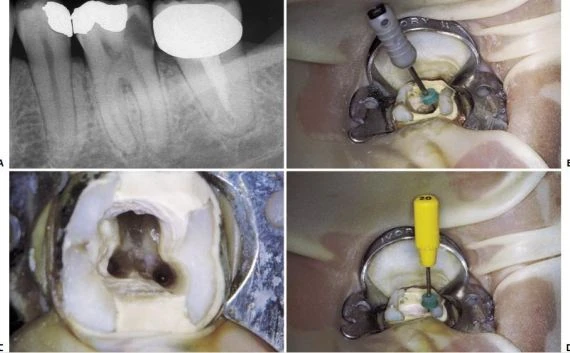

Ở những ống tủy cong, vị trí thành xoang đối diện với đoạn cong chân răng phải được mở rộng (hình 11.14). Nhằm đảm bảo dụng cụ không bị cong hơn so với độ cong vốn có của chân răng. Tương tự như lúc xe chạy vào khúc cua vậy, người ta thường tăng bán kính khúc cua để xe không bị chạy ra khỏi làn đường.

Hình 11.14. A. Phim trước điều trị R36: chân gần cong 1/3 trên. B. Mở đầu bằng trâm số #8 đi vào ống ngoài gần, nhận thấy ống tủy cong về phía xa và phía lưỡi. C. Xoang tủy được mở rộng về phía gần và phía má, phạm vào múi gần ngoài. D. Trâm số #20 có một đường vào thẳng đến 1/3 chóp của ống tủy.